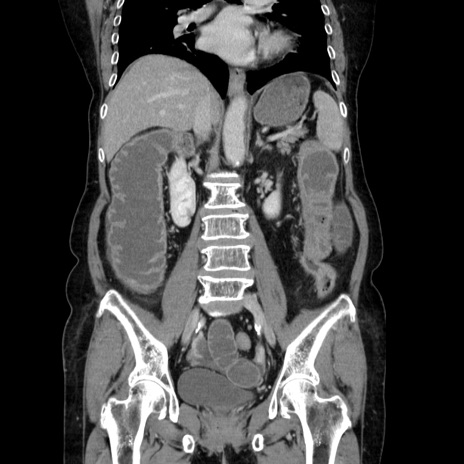

症例5(冠状断像)

【症例】70歳代女性

【主訴】お腹が張る

【現病歴】1週間くらい前から腹部膨満の自覚あり。昨日夜から増悪したため、本日救急外来受診。

【身体所見】意識清明、BT 36.5℃、BP 165/106mmHg、HR 80bpm、SpO2 98%、腹部:膨満、軟、自発痛・圧痛なし、触診にて不快感あり、腸蠕動音:減弱

【データ】WBC 12600、CRP 1.04